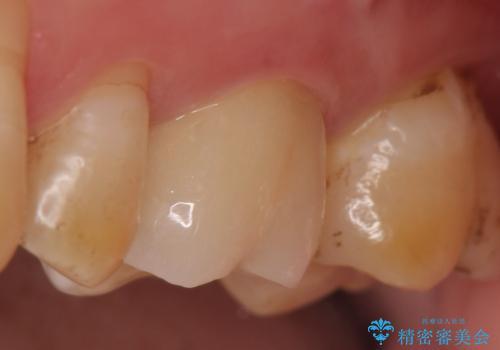

- 冷たいものを飲むと右下の奥歯が痛むので診て欲しいといらっしゃった方の症例です。

銀歯及び虫歯を除去後、より適合の良いPGA(ゴールド)インレーによる修復を行いました。